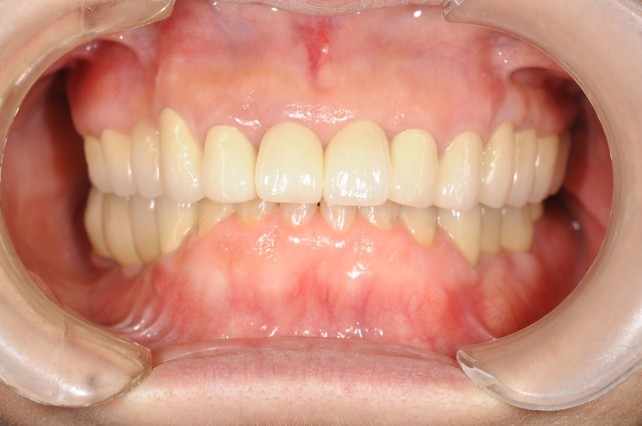

下顎臼歯部が欠損した患者さんのインプラント治療の症例②(うえだ歯科)

| 治療内容 | 下顎臼歯部欠損放置のため、臼歯部においてスペースがないため、全顎治療を行い咬合再構成を行う。 早期においてインプラント治療、咬合関係を模索した後、全顎にわたりセラミックによる補綴治療、その後メインテナンスに移行 |